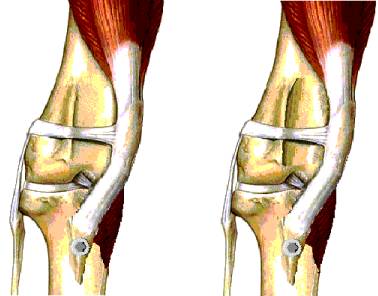

Tibial Crest Transposition (TCT). The patella tendon attaches to the top of the tibia. This area of bone is surgically separated from the shaft of the tibia and repositioned on the outside of the tibia. The bone is secured by pins and wires or a surgical screw. Recovery time to normal walking is 6-8 weeks although most dogs are weight bearing within 1 to 2 days.

Wedge Recession Trochleoplasty (WRT). The groove in the femur where the patella lies is surgically deepened by cutting out a wedge shaped section. |

Lateral ligament placement. This involves placing nylon bands through the patella and its tendon and anchoring them to the outside of the knee joint.

Any, a combination of, or all of the above techniques may be used to repair MLP. This decision is made during surgery and depends on the size of the dog, degree of luxation, conformation of the knee joint and the presence of osteoarthritis.

The prognosis following surgery is good to excellent in at least 95% of cases. Those cases that have a poorer prognosis are those with poor knee conformation, grade 3 and 4 luxations and those knees with osteoarthritis. |